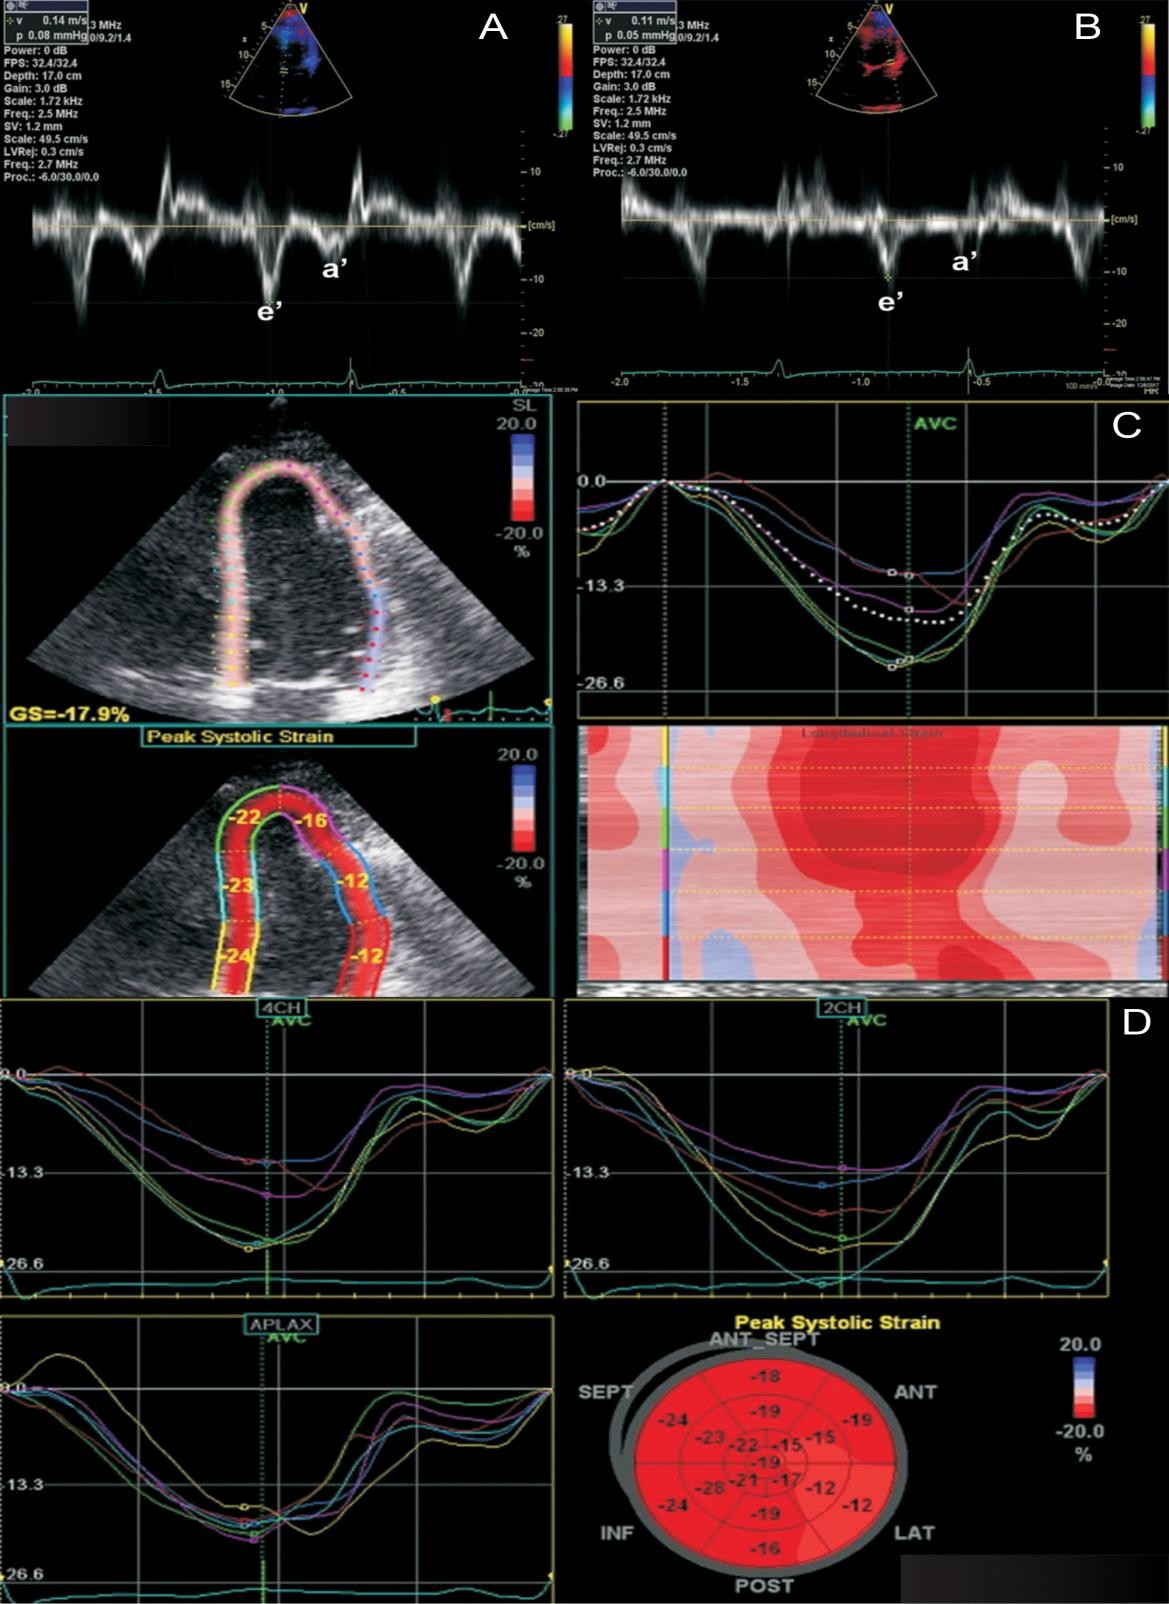

В диагностике констриктивного перикардита также может быть полезна тканевая допплерография, демонстрирующая так называемый феномен “annulus reversus”, заключающийся в том, что нормальная или повышенная ранняя диастолическая скорость движения медиальной части митрального кольца (медиальная е') оказывается выше, чем ранняя диастолическая скорость движения латеральной части фиброзного кольца (латеральная е’) (Приложение А3, рис. 3) [117].

Сочетание разнонаправленного смещения МЖП в зависимости от фаз дыхания с увеличением ранней диастолической скорости движения медиальной части митрального кольца (медиальная е') ≥9 см/сек имеет самую высокую диагностическую чувствительность (87%) и специфичность (91%) [118].

При эхокардиографическом исследовании для выявления констрикции перикарда могут быть использованы дополнительные показатели, в том числе деформация (strain). При констриктивном перикардите глобальная продольная деформация обычно сохранена, тогда как окружностная (циркулярная) деформация, скручивание и раннее диастолическое раскручивание снижены [119]. Этот тип нарушения деформации, “strain reversus”, является аналогом “annulus reversus”, выявляемым при проведении тканевой допплерографии. Показано, что это нарушение является обратимым после проведения перикардэктомии [119].

Допплер-ЭхоКГ позволяет определить парадокс кольца. Он заключается в том, что при относительном сохранении способности миокарда растягиваться в продольном направлении деформация продольной оси левого желудочка и продольная ранняя диастолическая скорость либо нормальные, либо, по мере прогрессирования констриктивного перикардита, увеличиваются. В то время как при рестриктивной кардиомиопатии или при заболеваниях миокарда происходит снижение этих показателей. При этом усредненная максимальная тканевая скорость раннего диастолического смещения септальной части митрального кольца выше латеральной (Приложение А3, рис. 6) [117, 123, 124–128]. Несмотря на высокую чувствительность и специфичность (95% и 96% соответственно), ограничение данного признака при диагностике будет проявляться в случае неоднородности поражения перикарда или при кальцификации кольца митрального клапана.